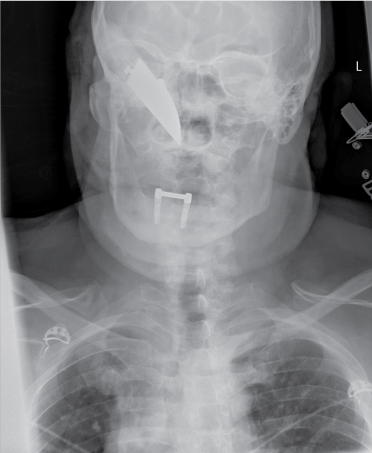

Because of the stable vital parameters we took the time to further investigate the knifeās trajectory. A plain X-ray showed the knife's position, outside the neurocranium, with the tip extending just anterior of the first cervical vertrebra (Figure 1 and Figure 2). To gain additional information regarding the structures in the face and the exact positioning of the knife a complementary enhanced CT scan with intravenous contrast was made (Figure 3). This scan showed the knife penetrating from the medial side of the orbita, along the maxillary sinus, through the medial pterygoid plate and nasopharynx, ending at the right anterior arch of C1. The eyeball and muscles are untouched, as well is the internal carotid artery.